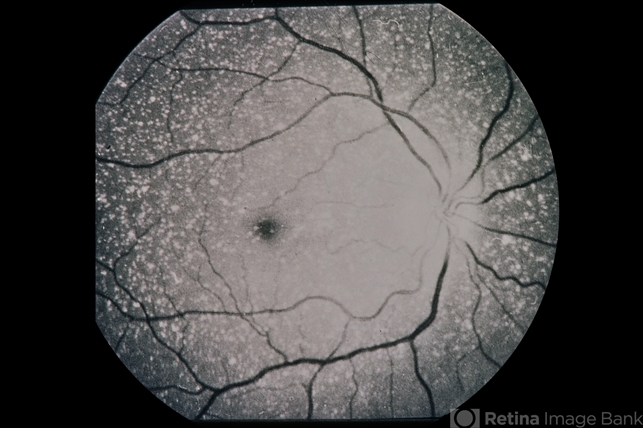

- Ring 17 Chromosome

- Condition/keywords

- crystalline retinopathy

- 3-year-old patient, crystalline retinopathy; 20/30 roughly; epilepsy.